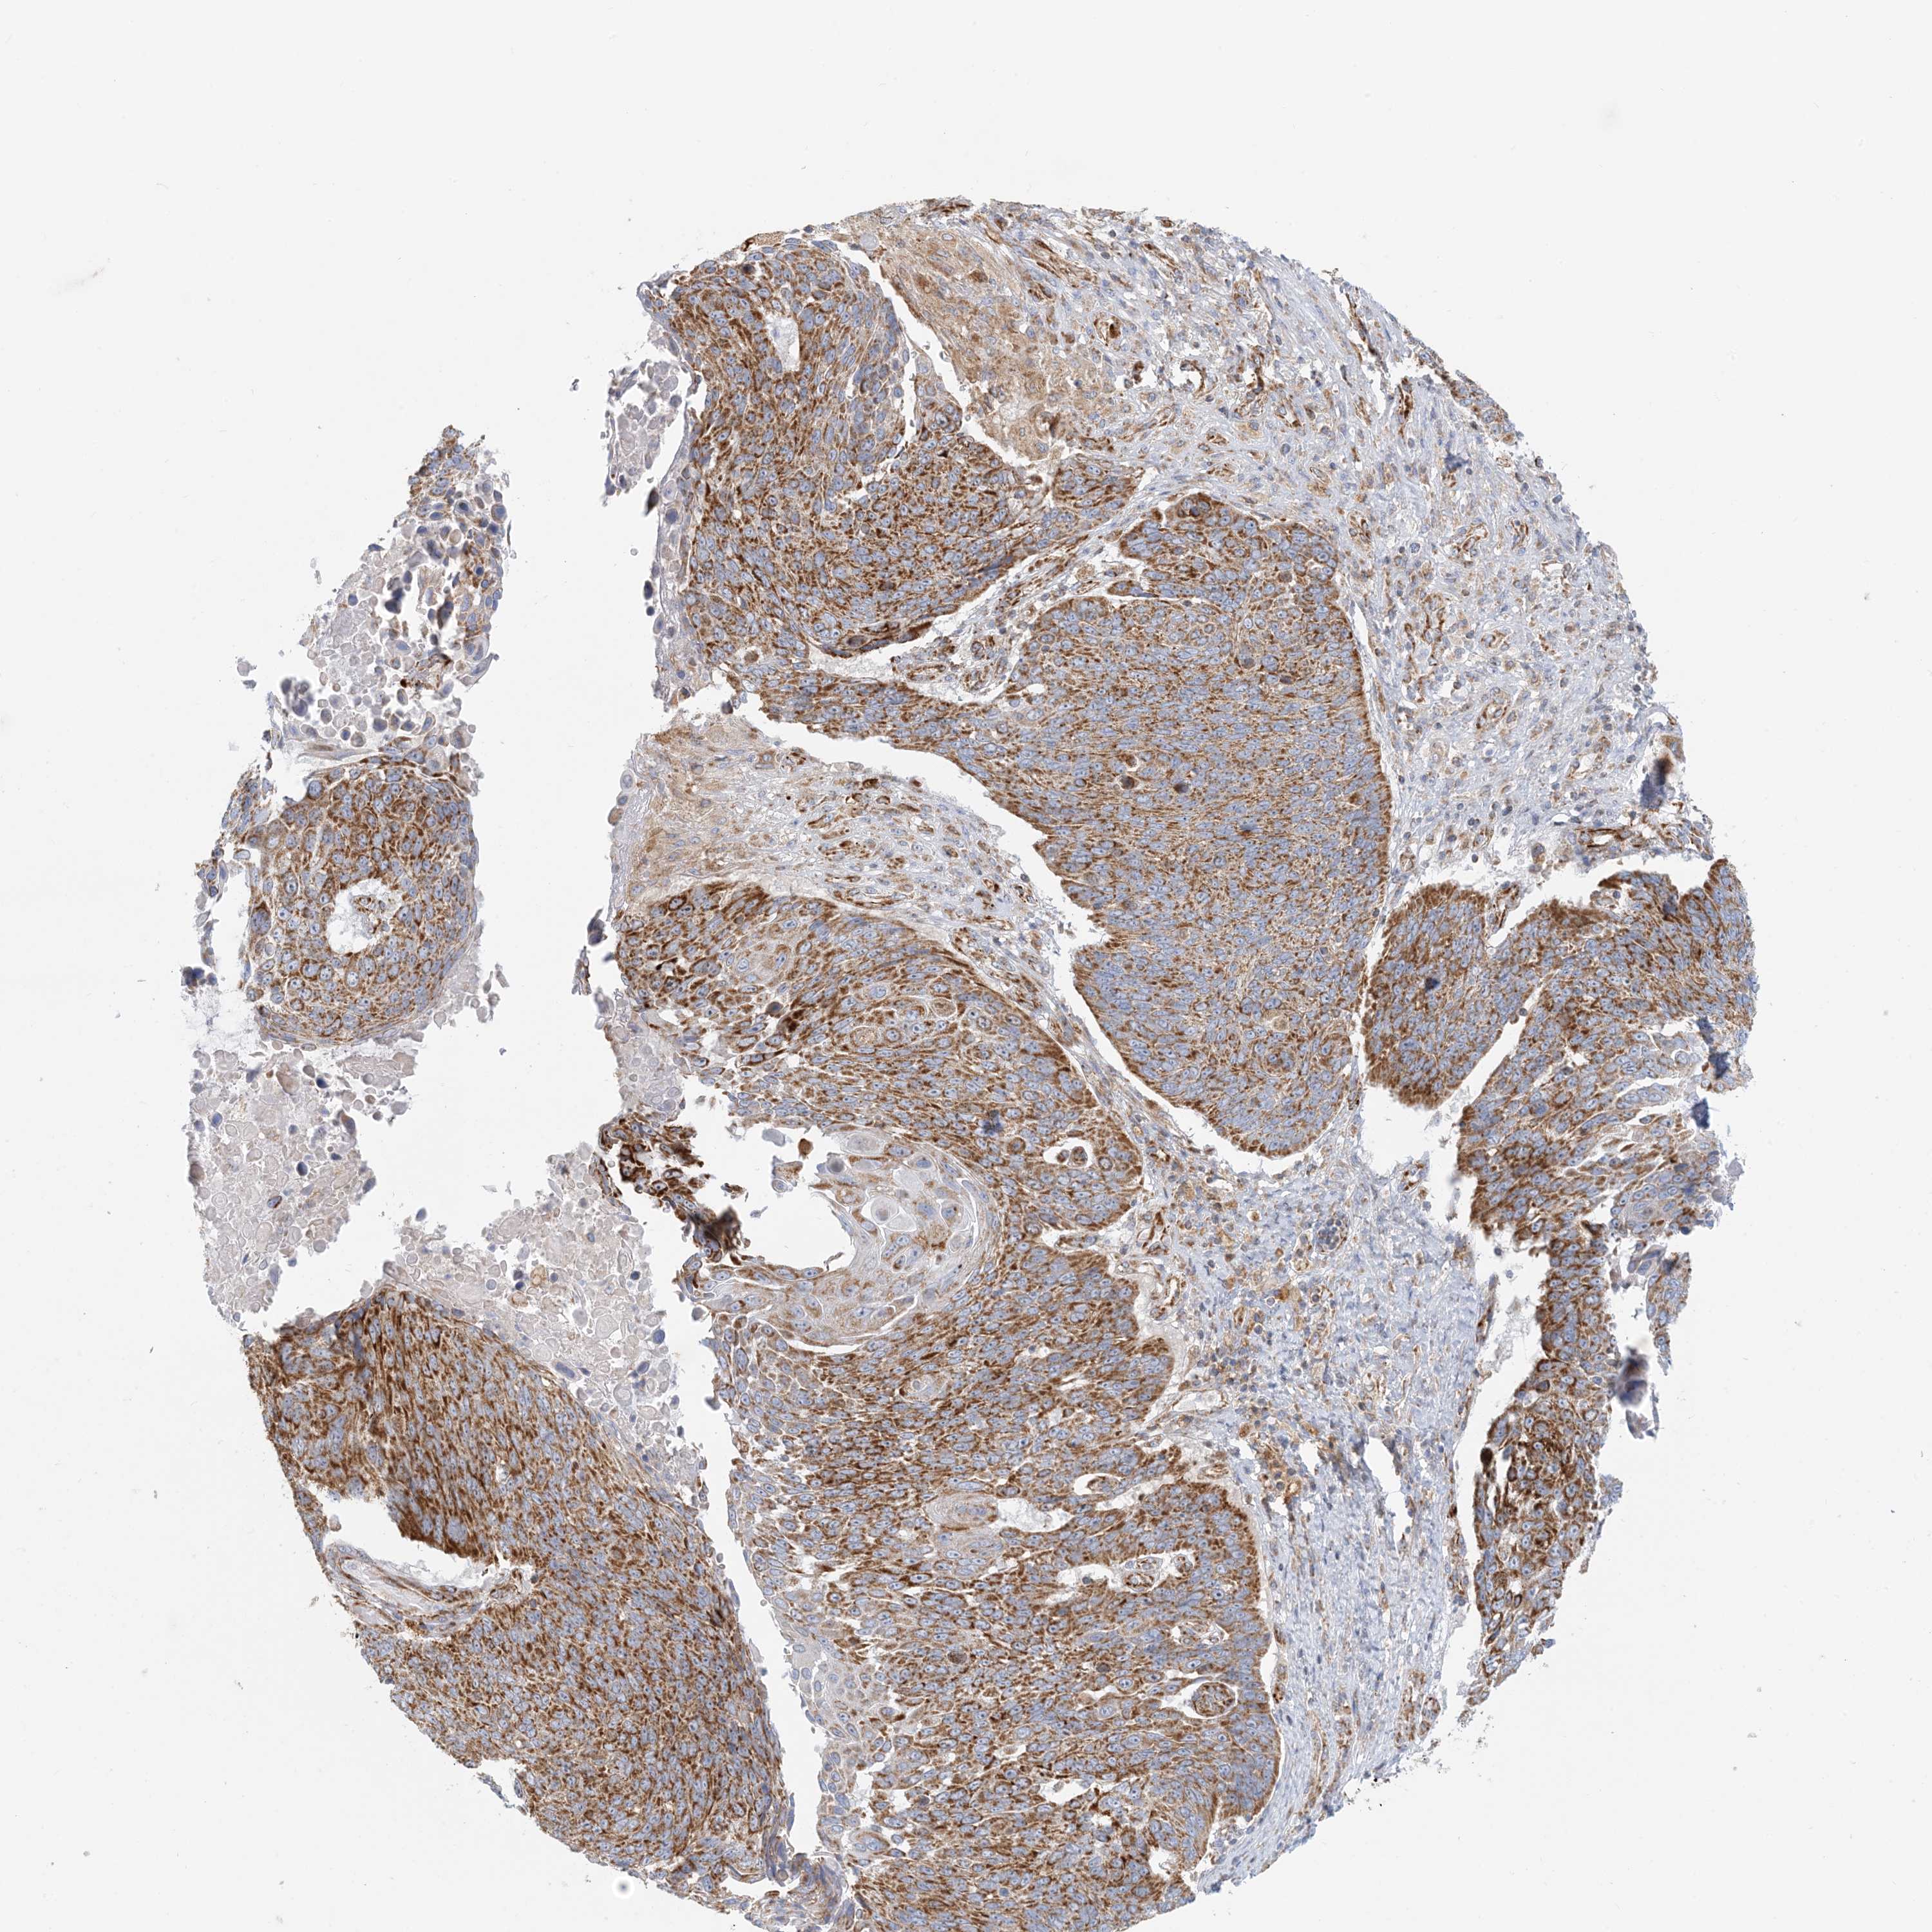

CANCER LUNG CANCER Show tissue menu

LUAD TCGA LUAD VALIDATION LUSC TCGA LUSC VALIDATION PROTEIN LUAD CPTAC PROTEIN LUSC CPTAC PROTEIN EXPRESSION

Lung cancer

Human cancer

Lung adenocarcinoma

Lung squamous cell carcinoma